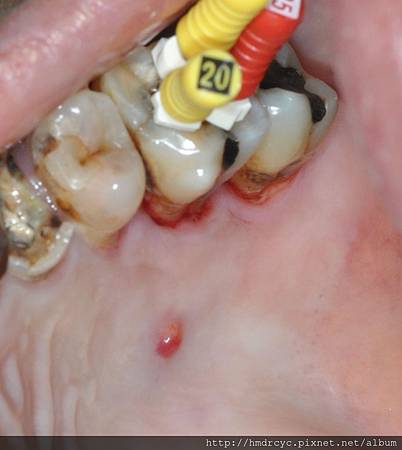

如果腫痛的部位有感染發炎

細菌多 化膿多 腫大嚴重

此時若將牙齒拔除

傷口本身潛藏的細菌

會回過頭來感染傷口

就算有吃藥 搭配沖洗

往往也沒有辦法完全維持乾淨

若是感染的狀況繼續擴大

反而可能發展成蜂窩性組織炎

嚴重的話需要住院

甚至有致命的危險

所以有感染發炎痛

欣美牙醫不建議拔牙

需要先局部清潔沖洗

吃三天分消炎止痛藥

等腫消了再來做拔牙